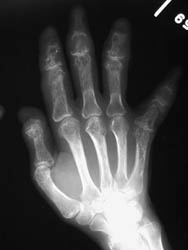

Sarcoid is a multisystemic disease of unknown etiology which results in noncaseating

granulomas found throughout various organ systems including the osseous structures.

This process occurs approximately ten times more frequently within the black

population with an increased female predominance.

The hands are the most common site of osseous involvement. The middle and

distal phalanges and less frequently the proximal phalanges and metatacarpals

may show changes associated with sarcoidosis. Involvement at the wrist occurs

much less frequently.

An abnormal trabecular lace-like pattern of destruction can often be seen

at the phalanges and metacarpals of the hands. Cystic changes and osseous

destructive lesions may also be evident. Acro-osteosclerosis with the radiographic

appearance of terminal phlangeal sclerosis is not specific; however, it has

been reported in up to half of the patients with skeletal abnormalities of

sarcoidosis. Soft tissue swelling, and inflammatory skin nodules (erythema

nodosum) are occasionally noted. If the wrist is involved, cystic changes

and lytic lesions may be present.

The abnormal trabecular pattern of destruction at the hands is fairly characteristic of sarcoidosis. If osseous destruction is present at the distal phalanges, the appearance may be similar to findings associated with scleroderma. However, scleroderma has fairly characteristic associated soft tissue findings which distinguish it from sarcoidosis.